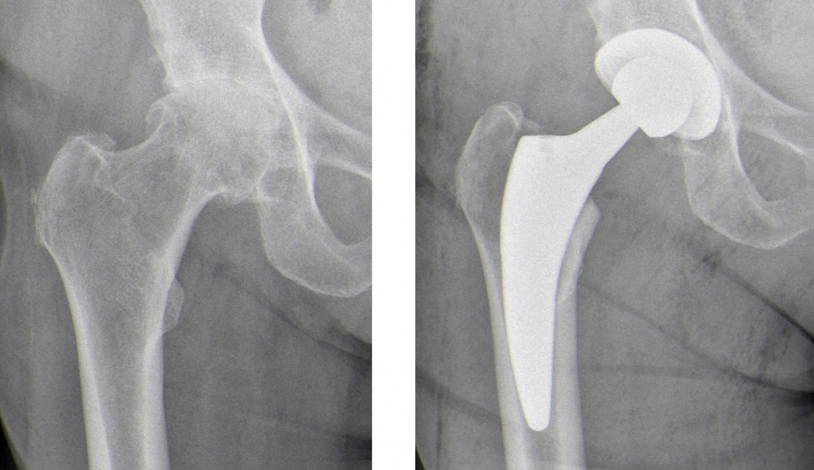

Die richtige Hüftendoprothese - individuell für jeden Patienten

Der endoprothetische Ersatz des Hüftgelenks gilt als eines der erfolgreichsten Operationsverfahren überhaupt. Hierbei wird sowohl die Hüftpfanne als auch der Hüftkopf ersetzt. Fortschritte im Design von Hüftgelenksendoprothesen sowie neuere OP-Techniken mit minimal invasiven Zugängen ermöglichen eine individuelle auf die Bedürfnisse des Patienten zugeschnittene Behandlung. Die Wahl der Endoprothese richtet sich hierbei nach dem Alter, der Knochenbeschaffenheit sowie dem körperlichen Aktivitätslevel.

Bei normalen knöchernen Verhältnissen ist eine zementfrei verankerte Hüftendoprothese der Standard. Die knöchern verankerten Komponenten (Schaft und Pfanne) bestehen hierbei aus gut verträglichen Titan. Die direkte Verbindung von Schaft und Pfanne erfolgt über eine Hüftkopf aus Keramik und ein Polyethyleninlay (Gleitpaarung).

Bei deutlich reduzierter Knochenqualität erfolgt eine Verankerung des Prothesenschaftes über einen speziellen Knochenzement. Hier besteht der Schaft aus einer Kobalt-Chrom-Legierung. Eine Zementierung der Pfanne ist nur in Ausnahmefällen notwendig.

Alle verwendeten Materialien zeichnen sich durch eine sehr gute Gewebeverträglichkeit und geringen Abrieb aus.